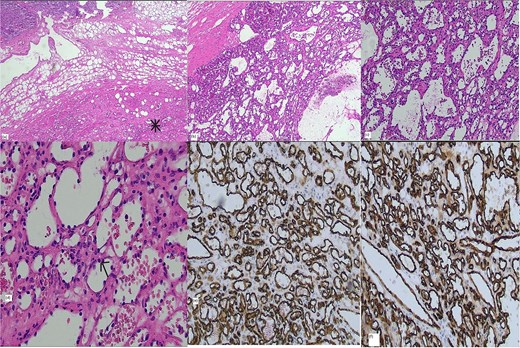

It is commonly diagnosed postoperatively by histologic examination, which requires differentiation from aggressive angiosarcoma. Grossly, they are well-circumscribed hemorrhagic lesions and histologically show prominent hobnailing of endothelial cells with anastomosing sinusoidal spaces without evidence of atypia or invasive malignancy. Recent retrospective study of 13 anastomosing hemangiomas showed GNAQ gene mutation as a driver for pathogenesis of anastomosing hemangioma, which is not found in angiosarcoma [5]. This could potentially be useful in preoperative biopsy to distinguish from angiosarcoma (Fig. 2).

Histology: (a) Hematoxylin and eosin (H&E) stain × 2 magnification showing interface of adrenal (top) and vascular lesion (bottom), (b) H&E stain × 4 magnification (c) H&E stain × 10 magnification, (d) H&E stain × 20 magnification, positive vascular endothelial immunohistochemical markers CD 31 (e) and CD 34 (f).